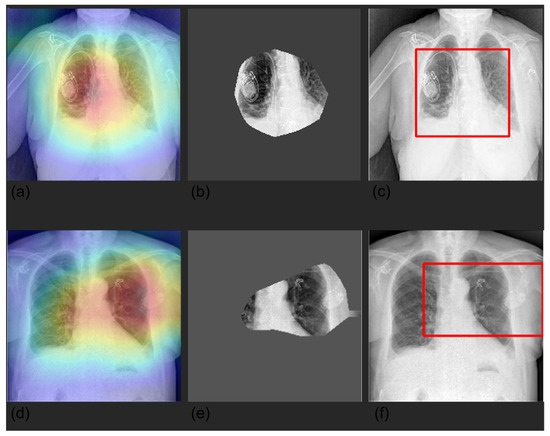

3.4. Grad-CAM